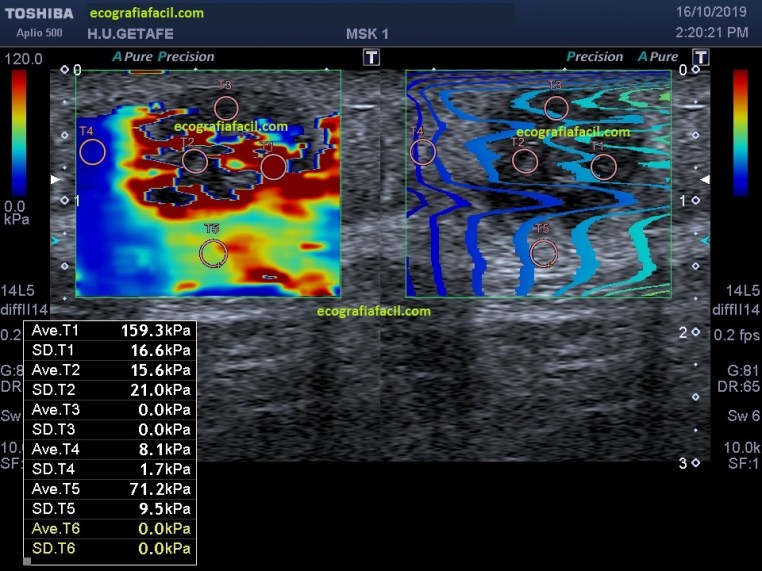

Una vez finalizado el estudio habitual, quiero contarte como se ve esta lesión estudiada con Elastografía. El estudio elastográfico que ves en la imagen 6 y 7 desvela cosas muy importantes y nos sirve de repaso de esta técnica y su aplicación a otras patologías, no solo a la ecografía muscular.

Lo que llama poderosamente la atención en la imagen 6, que es el elastograma, es el color rojo intenso, que marca la dureza o poca elasticidad en la LOE a estudio.

Al lado, en el elastograma de ondas, se percibe claramente una distorsión de las ondas, mucho más llamativo en la zona superior de la LOE, que si comparamos con la imagen del elastograma de color vemos que la zona de la lesión que no se colorea en rojo corresponde con la zona de máxima distorsión en las imagen de las ondas.

¿Qué explicación tiene? muy sencillo, cuando la lesión es muy dura, en ocasiones lo es tanto, que el elastograma de color no hace la lectura, sin embargo en el elastograma de ondas se objetiva que las ondas se modifican sustancialmente, haciéndose más curvas, la lectura que podemos hacer es que en el contexto de una lesión dura, o poco elástica, en su porción más superior, lo es mucho más…

Cuando hacemos la lectura con los rois, en la imagen 7, y colocamos hasta 5 rois, tenemos diferentes lecturas que quiero que estudies muy atentamente antes de desvelarte los secretos de estos datos…ahora observa, donde están colocados los rois y su valor, en este caso en Kilopascales que es una medida de presión, también podemos hacerlo en velocidades.

T1: Colocado en zona coloreada de rojo, profunda, con un valor alto de 159 kPa. Marca zona poco elástica.

T2: Zona no coloreada, a la altura de T1, parece valor bajo de 15,6 kPa a la altura de T1, se observa modificación en la curva de la onda donde marca una zona más blanda de la lesión que corresponde con la lectura del Roi.

T3: Zona no coloreada, superficial, sin lectura, corresponde con la zona de no color en elastrograma y zona de máxima distorsión de la onda, la lectura es clara, es la zona más dura de la LOE, es tan dura que la escala del ROI no puede leerla, esta lectura aunque marque 0 es coherente y sabemos que es un valor superior a 200 kPa en este equipo. En cicatrices musculares de largo tiempo de evolución, muy habitualmente, esta lectura ya no es posible por la poca elasticidad de éstas ya que siempre se sitúan por encima de 200 kPa.

T4: Zona coloreada de azul intenso, fuera de la LOE, las curvas del elastograma de ondas son muy suaves, casi rectas y la lectura es de 8kPa, en referencia clara a la grasa circundante de la lesión, que aunque pueda estar infiltrada es muy elástica, muy blanda, es una lectura coherente claramente.

T5: Zona de coloración intermedia, con valor de lectura que ronda los 71 kPa, intermedia, en el elastograma de curvas la onda es suave, homogéneamente suave en ese tramo en la profundidad de la imagen, que en la imagen 1, puedes ver que corresponde con la fascia profunda. Lectura globalmente coherente en el contexto normal de una fascia.